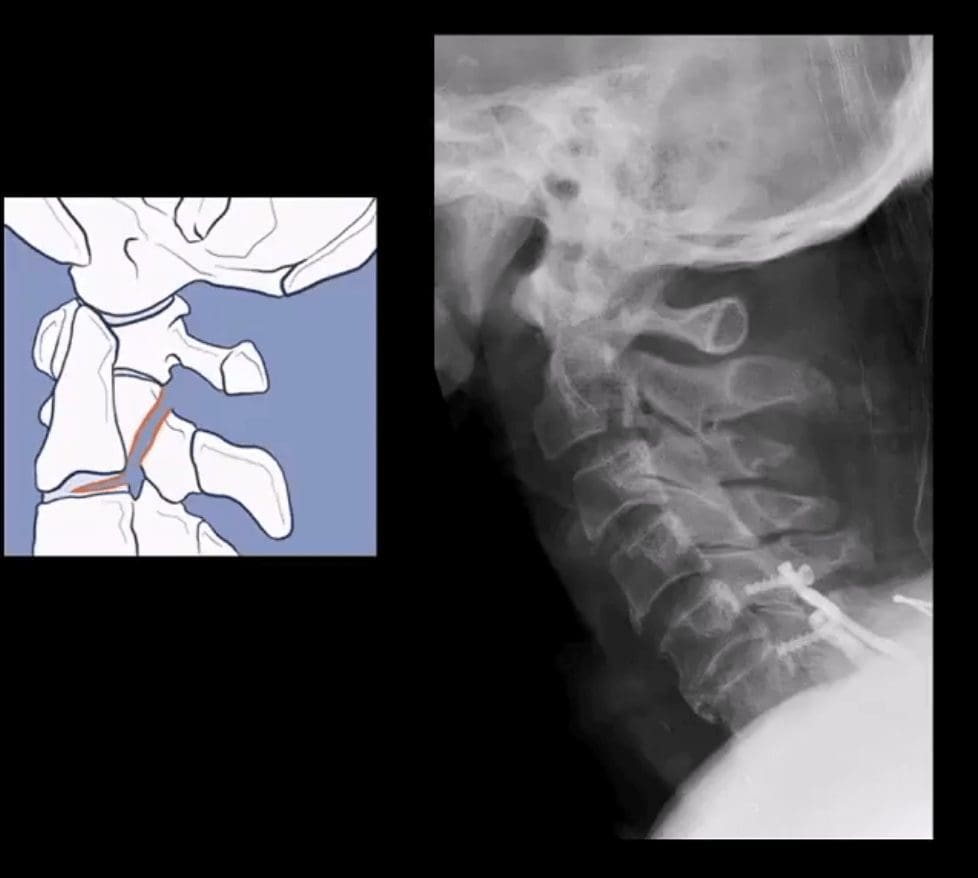

- Hangman’s Fx aka traumatic spondylolisthesis of C2 with a fracture of pars interarticularis or pedicles (unstable)

- Mechanism: acute hyperextension of upper C/S similar to judicial hanging (never actually seen and most deaths are due to asphyxiation)

- Secondary flexion may tear PLL and disc

- Associated injuries: 30% have other c-spine fx especially Extension teardrop at C2 or C3 due to avulsion by ALL

- Cord paralysis may only present in 25% due to bony fragments dissociation and canal widening

- Hangman fx and extension teardrop

- Cervical degeneration and previous fusion is a key predisposing factor due to the lack of mobility and suppleness, rendering C/S easy to fracture

- Imaging: initial x-radiography then CT that helps to delineate another injury such as facet/pedicle Fx further. MRI may help if complicated by Vertebral A. damage

- Management: if type 1 injury then closed reduction and rigid collar for 4-6 weeks, halo bracing if type 2 (>3-5mm displacement) Fx/instability, anterior or posterior spinal fusion at C2-3 if type 3 Fx (>5-mm displacement)

- Extension teardrop Fx (stable) potentially unstable if put in extension

- Avulsion of an inferior anterior body by ALL. More seen in elderly with superimposed C/S spondylosis

- Key radiography: a smaller anterior-inferior body corner, no disruption of ligamentous alignment. Typically at C2 or C3 due to sudden hyperextension and ALL avulsion

- Complication: central cord syndrome (m/c incomplete cord injury) esp. in superimposed spondylosis and canal stenosis by the laxity of ligamentum flavum and osteophytes

- Management: hard collar isolation